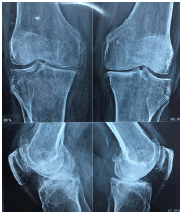

Paciente mulher com 68 anos, IMC 32, apresenta dor crônica em joelhos, com piora progressiva, interferindo na marcha. Ausência de outras queixas articulares. A radiografia simples em incidências anteroposterior e perfil são demonstradas na imagem abaixo.

Diante das características clínicas e radiográficas desta paciente, analise as proposições abaixo e responda o que se pede.